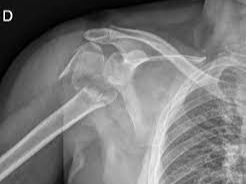

어깨뼈 골절은 어깨 주변을 구성하는 여러 뼈 중 하나가 부러지는 상태를 의미합니다. 어깨는 단순한 관절이 아니라 여러 뼈와 인대, 근육이 복합적으로 연결된 구조이기 때문에 골절의 종류도 다양하게 나타납니다. 흔히 발생하는 골절 위치는 견갑골, 쇄골, 상완골 근위부입니다. 특히 낙상 사고나 교통사고에서는 상완골 근위부 골절이 자주 발생합니다.

이 중에서도 상완골 근위부 골절은 고령자 낙상 사고에서 매우 흔하게 나타나는 골절이며, 경우에 따라 금속 핀이나 금속 플레이트를 이용한 고정 수술이 필요할 수 있습니다.

- 초기 진단

- X-ray 촬영

- CT 검사

- 골절 위치 확인